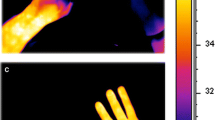

Infrared thermography

A Anterior view of thoracic segments diagram, showing the representative rectangle areas (RAs) measured by infrared thermography. B thermographic image of a 41-yr-old male patient. (a) thermographic image before thoracic paravertebral block; (b) thermographic image at 15 min after thoracic paravertebral block. Grey arrow indicated the blocked side

Temperature difference (Td) was defined as the difference of skin temperature between the blocked side and the unblocked side at a certain dermatome. Td was calculated at each measurement time point for each dermatome. A characteristic infrared thermographic image before and after the block was shown in Fig. 1B.